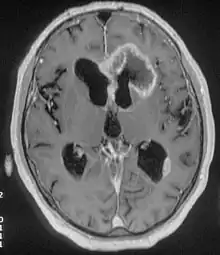

There are many different causes of frontal lobe epilepsy ranging from genetics to head trauma that result in lesions in the frontal lobes.[4] Although frontal lobe epilepsy is often misdiagnosed, tests such as prolonged EEG monitoring, video EEG and/or an MRI scan of the frontal lobes can be administered in order to reveal the presence of a tumor or vascular malformation.[4] Unlike most epileptic EEGs, the abnormalities in FLE EEGs precede the physical onset of the seizure and aid in localization of the seizure's origin.[4] Medications such as anti-epileptic drugs can typically control the onset of seizures, however, if medications are ineffective the patient may undergo surgery to have focal areas of the frontal lobe removed.[4]

- MRI

Neuroimaging for diagnosis

Advancements in technology, has given rise to newer, more efficient methods of diagnosis, most prominent being in the domain of neuroimaging.[8] The high spatial resolution from fMRI has implications on certain brain regions contributing to memory.[8] The usage of task fMRI for examination of memory or other higher cognitive networks may also be used to predict ictal onset zone(s) in patients with FLE, giving the advantage of refinement of patient-specific analyses.[8] The use of multi-modal approaches in association with neuroimaging techniques like fMRI and MEG or EEG will be informative in characterizing atypical functional brain networks in FLE.[8] But, difficulty remains in the evaluation of potential compensatory mechanisms between patients with FLE with normal and impaired memory, without properly characterizing transfer of information during memory tasks.[8]